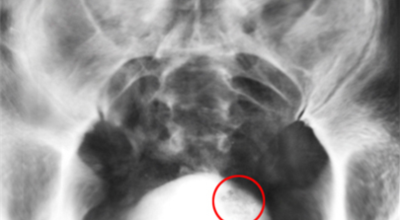

3. 방광암 초기증상 - 혈뇨

혈뇨는 소변을 눈으로 확인했을 때 빨갛게 관찰되는 것을 육안적 혈뇨라고 하고 눈으로 보기에는 깨끗하지만 소변검사를 했을 때 혈뇨관 소견으로 관찰되는 현미경적 혈뇨로 구분돼요. 2가지 혈뇨 현상 모두 방광암의 증상으로 볼 수 있으며 이러한 증상이 발생하게 되면 병원의 정밀 검진이 필요합니다. 소변의 색은 붉은색으로 보이기도 하고 녹색으로 보이기도 합니다.